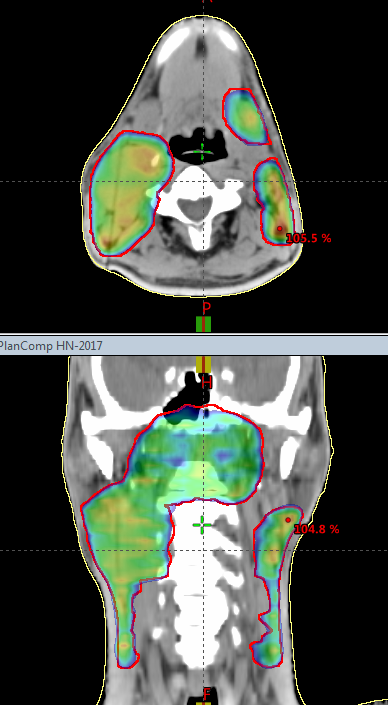

Jonathan Stenbeck

Score: 99.0/ 100

Greenville Health System

Technique: VMAT

Rank: Third Top (Eclipse)

Job Title: Medical Physicist